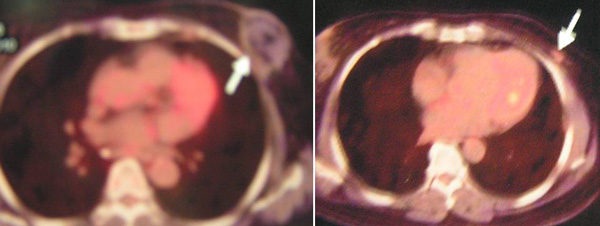

Riwayat medis

Pasien ini terdiagnosa kanker payudara yang telah menyebar ke tulang-tulangnya. Dia pergi ke Cina untuk berobat – menggunakan kemoterapi, cryoablation dan radioactive particle seed implant. Pada tahun 2008, dia pergi ke Cina sebanyak tiga kali, dua kali di tahun 2009 dan satu kali di tahun 2010. Pengobatan ini tidak lantas membuatnya sembuh. Sejak bulan Februari 2011, dia tidak bisa berjalan. Kaki sebelah kirinya sakit dan bengkak. Dua bulan kemudian dia menjalani operasi untuk kaki sebelah kirinya. Namun sakitnya tidak hilang.

Dokter di Kuching menyarankan untuk menjalani kemoterapi. Tetapi dia menolak. Keluarga memutuskan untuk membawanya ke China untuk perawatan medis. Dia menerima perawatan seperti kemoterapi, cryoablasi dan particle seed radioaktif di rumah sakit China.